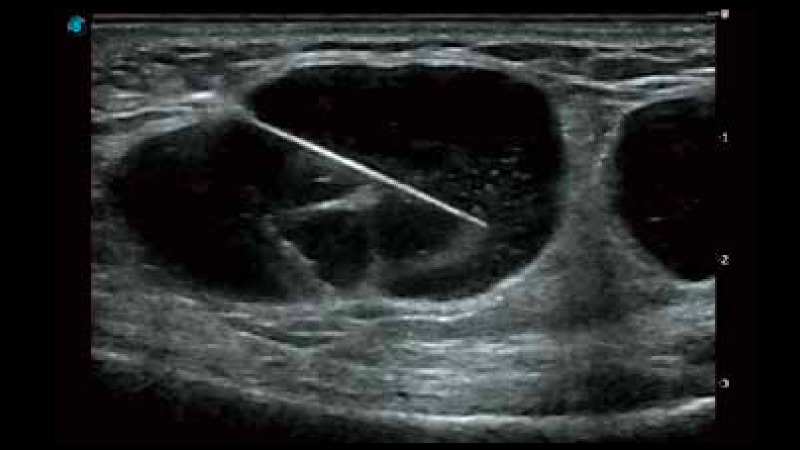

穿刺增强

穿刺增强通过超声波光束控制和偏转,增强了针头在组织中的显像效果。从而保证在穿刺过程中最大限度减少对周围组织的伤害,降低穿刺风险,提高穿刺成功率。

临床图像